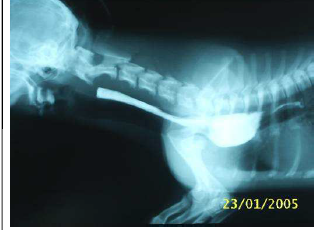

Observe esta radiografia contrastada:

Esta imagem é típica de uma afecção comum em cães. Há uma sombra menos radiopaca abaixo do contraste que serve de orientação. O que representa a porção contrastada?